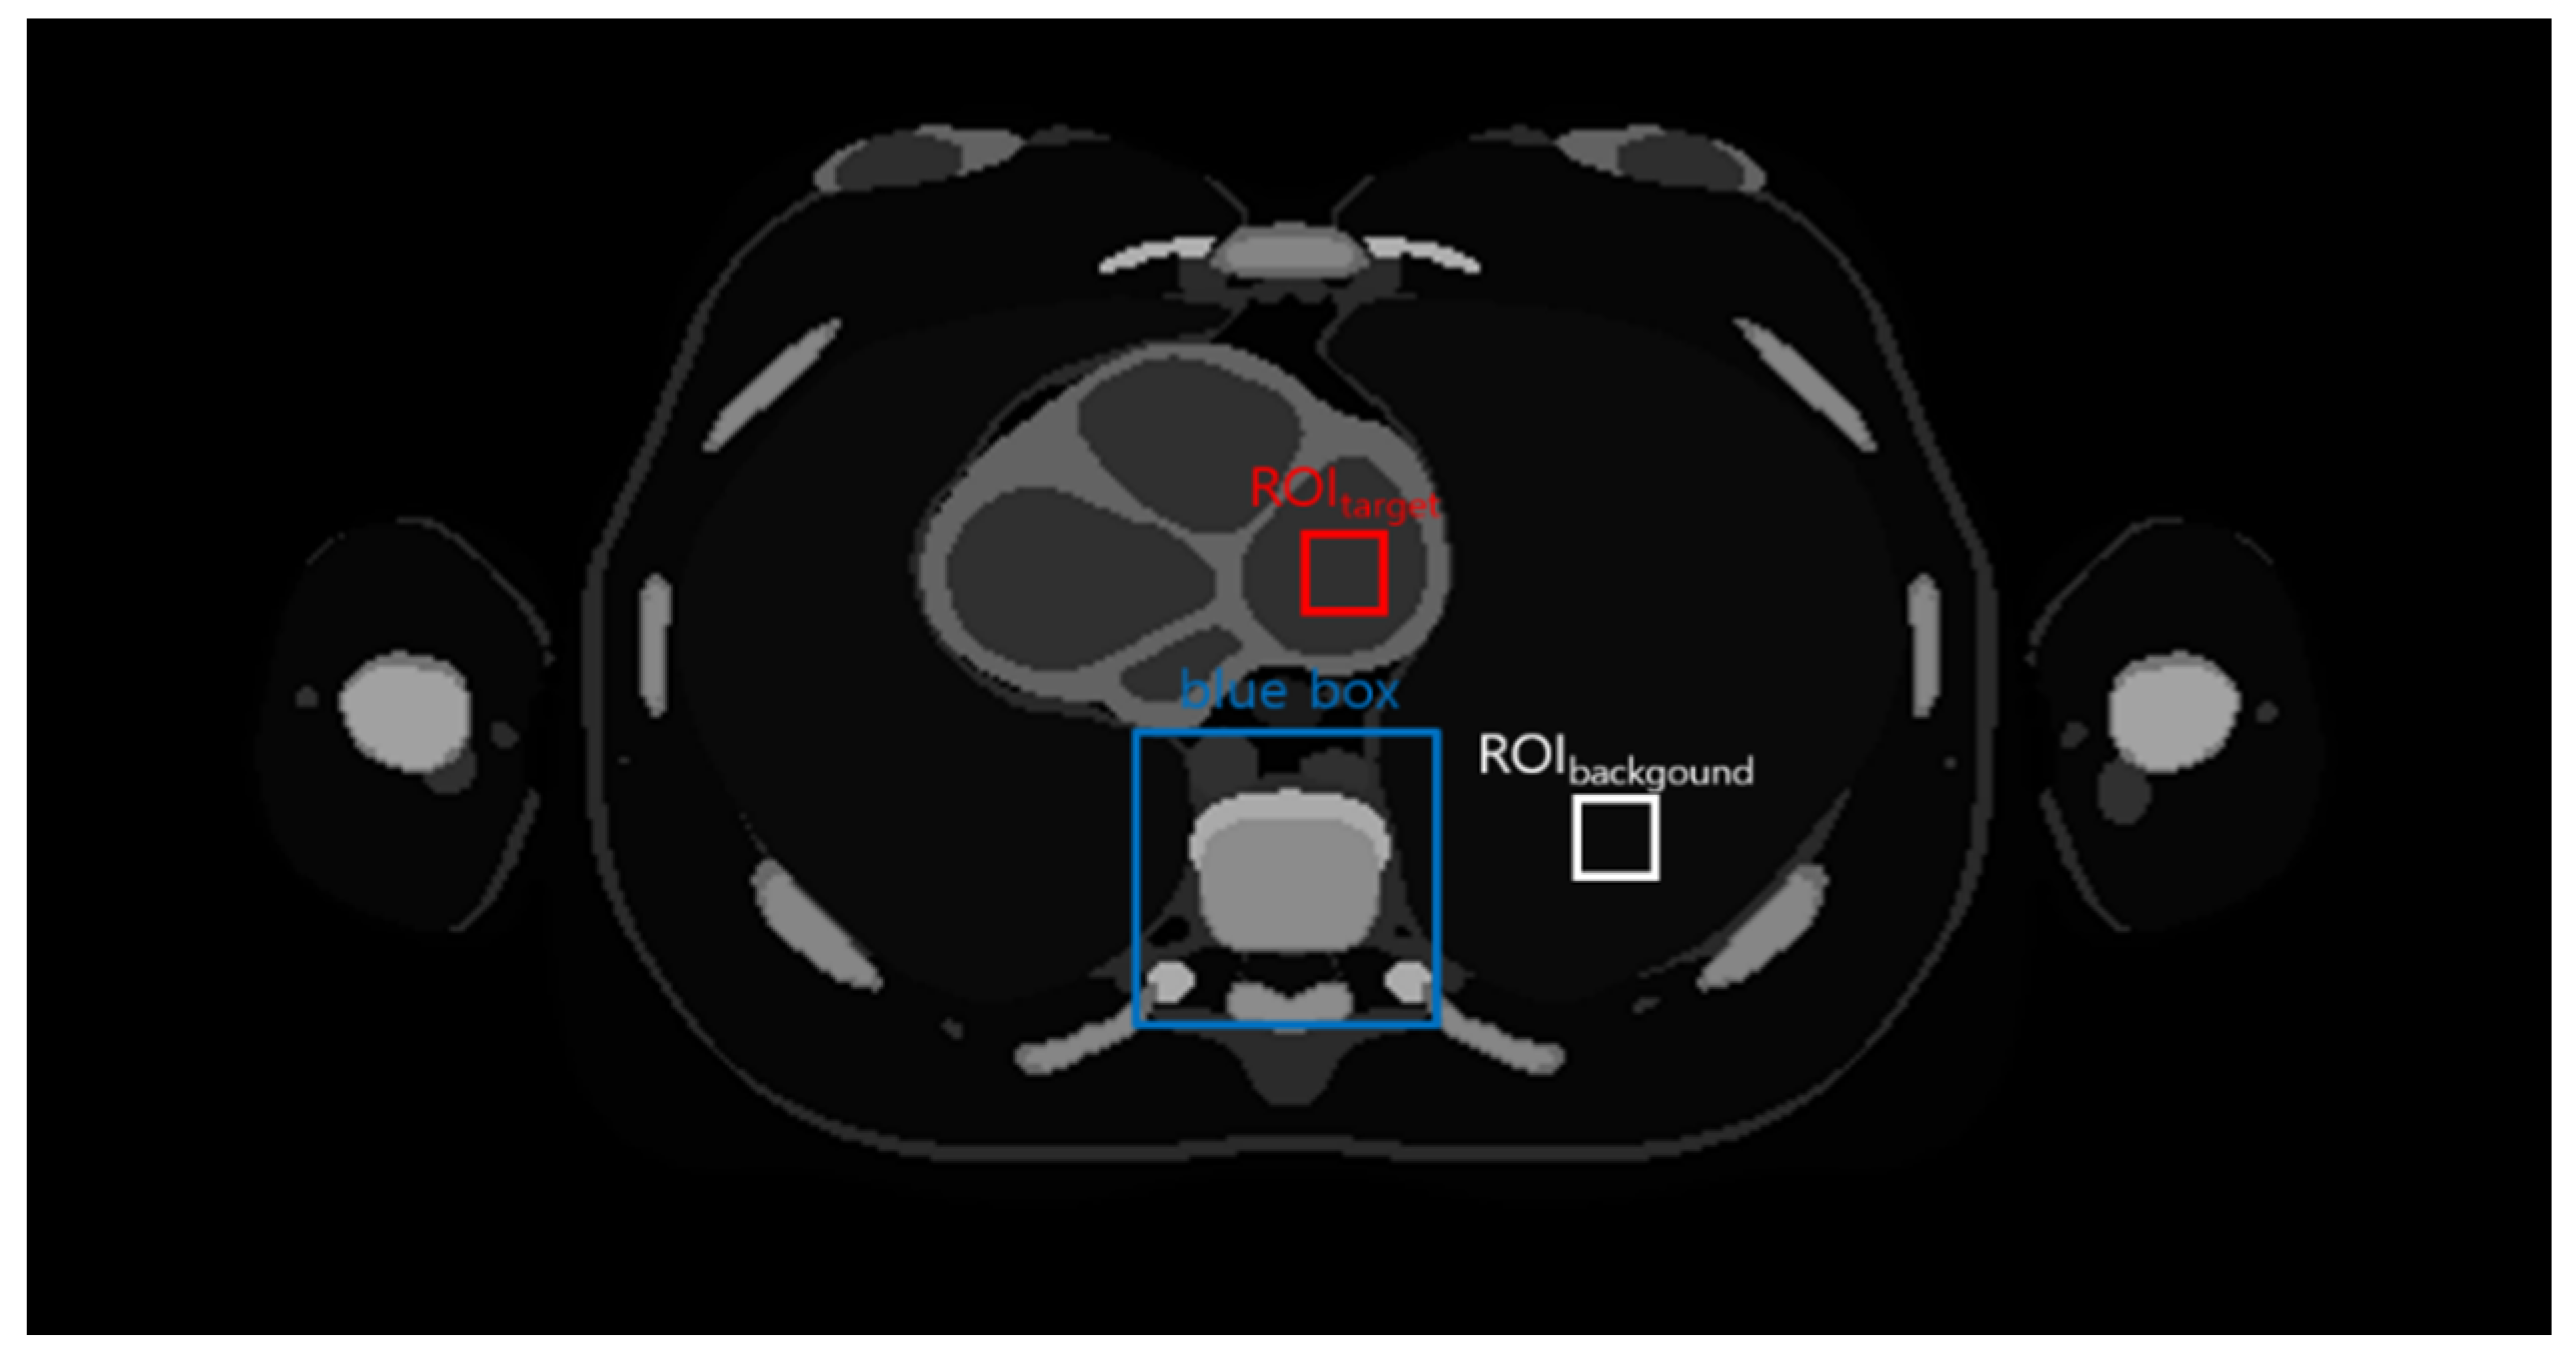

2.1. Acquisition of the Thoracic Image from the Male Adult Mesh (MASH) Phantom: The Simulation Study

2.4. Quantitative Evaluation Factors

2.4.1. Evaluation Factors for the Noise Level